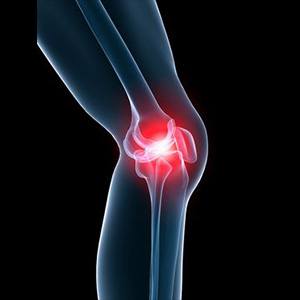

Picture of Knee Pain

Knee Pain

Knee pain is a common condition affecting individuals of various age groups. It not only affects movement but also impacts your quality of life. An injury or disease of the knee joint or any structure surrounding the knee can result in knee pain. A precise diagnosis of the underlying cause is important to develop an appropriate treatment plan.